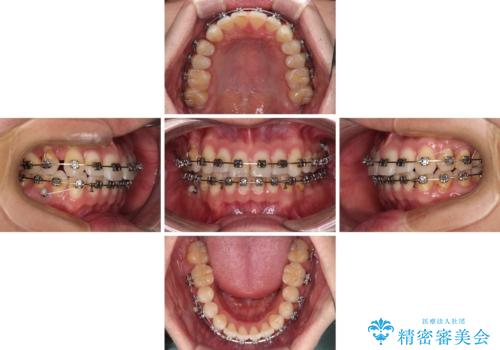

- 以前矯正治療を行ったものの、思い通りの仕上がりではなく、更には後戻りが気になってきたとのことで来院された患者様です。

上顎右側の第一小臼歯が動きにくい歯であり、以前矯正治療を行った際に傾斜した位置のまま終了したことと、それに伴い後戻りで歯列が波打っているようになっていることを大変気にしていらっしゃいました。

咬合平面改善のため、アンカースクリューを多用し、ワイヤー装置にて矯正治療を行うこととしました。